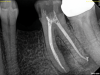

Just as systemic conditions and patient habits impact outcomes after NSRCT, the local dental environment and dental disease states also impact outcomes (Figure 1 through Figure 5). In the Toronto study evaluating 4- to 6-year outcomes following NSRCT, the presence of a periapical radiolucency emerged as a key prognostic factor, substantially reducing the success rate by a factor of four.12 Single-rooted teeth experienced better outcomes compared to multirooted teeth in the presence of periapical lesions.1 Teeth diagnosed preoperatively with irreversible pulpitis or necrosis, in the absence of AP, showed a more favorable prognosis compared to those with preoperative AP.2

Fig 1. NSRCT can have high success, even with risk factors like periapical pathology associated, as depicted in this case presentation. Fig 1: Preoperative periapical radiograph showing AP. Fig 2: Preoperative CBCT. Fig 3: Immediate postoperative periapical radiograph. Fig 4: Three-month follow-up CBCT showing reduction of periapical radiolucency. Fig 5: One-year follow-up periapical radiograph showing resolution of periapical radiolucency.

Figure 1